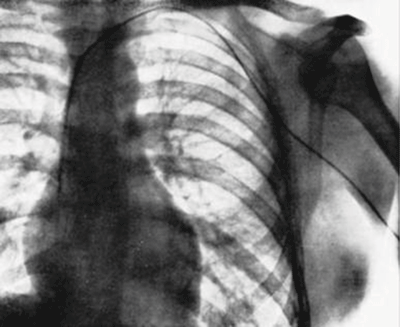

Following this, Forssmann somehow managed to one-handedly release Ditzen – who had apparently realised what was happening at this point – and he told her to call the X-ray department. The two of them then excitedly walked down to the X-ray department (it was one floor below where they had started this madcap adventure). Once there, with the help of a fluoroscope (an Xray-like instrument), Forssmann continued to advance the catheter a full 60 cm into his arm. It crossed his chest and entered the right ventricle of his heart. To record this amazing achievement they made an X-Ray before the catheter was removed.

Ladies and gentlemen, the X-ray:

Forssmann’s X-ray image. Source: Jbsr